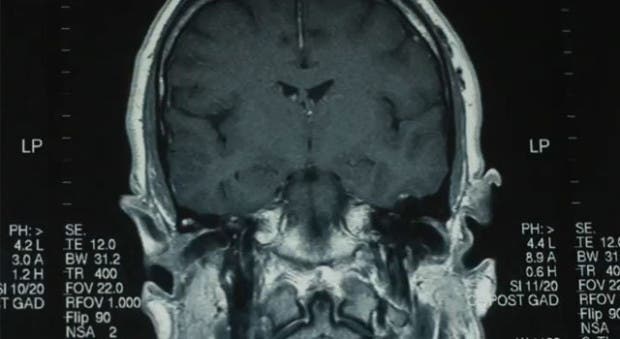

Tras una resonancia magnética se confirmó el cáncer, y empezó a tratarse.